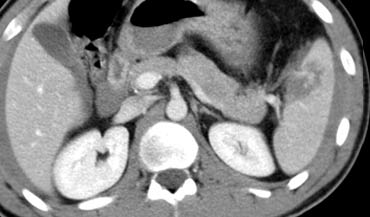

Trước tiên hãy quan sát các hình ảnh bên trái của bệnh nhân bị chấn thương gan.

Các dấu hiệu CT trong trường hợp này là gì?

Các dấu hiệu bao gồm:

- Tụ máu dưới bao gan lớn hơn 10 cm (tức là tổn thương độ 4)

- Vùng ngấm thuốc cản quang (contrast blush) (mũi tên)

- Không có tràn máu ổ bụng kèm theo

Vì vậy, mặc dù có thoát thuốc cản quang, bệnh nhân này sẽ được điều trị bảo tồn (không phẫu thuật) và có thể có tiên lượng tốt, do không có chảy máu vào khoang phúc mạc.

Thoát thuốc cản quang có ý nghĩa đặc biệt quan trọng, nhất là khi kết hợp với tràn máu ổ bụng.